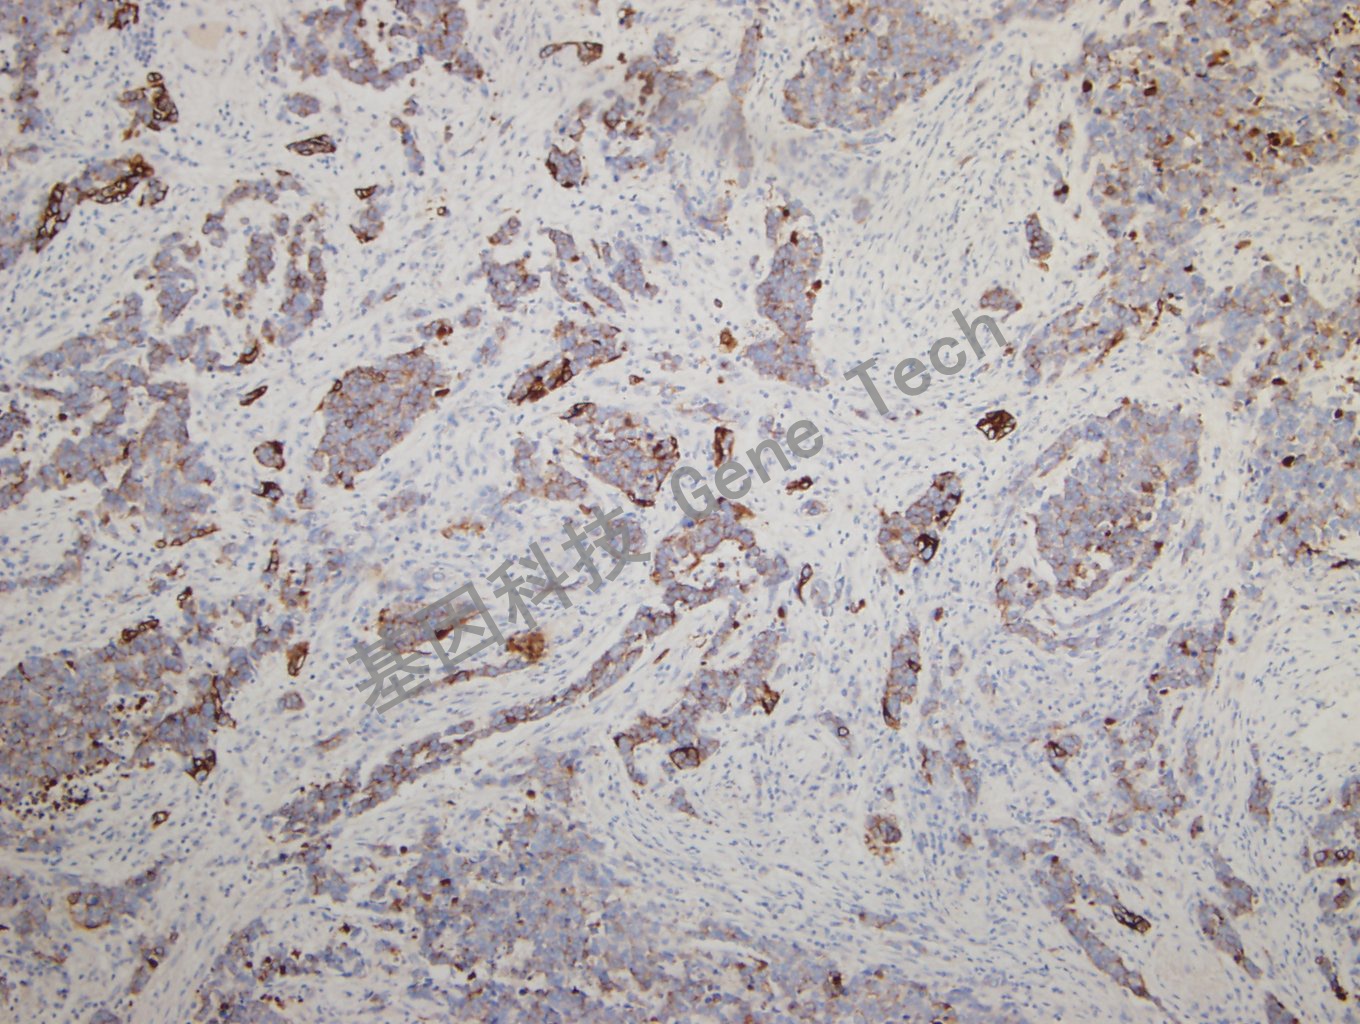

肺腺癌石蜡切片,用 CK,pan(GM3515)染色,细胞浆阳性,DAB 显色。